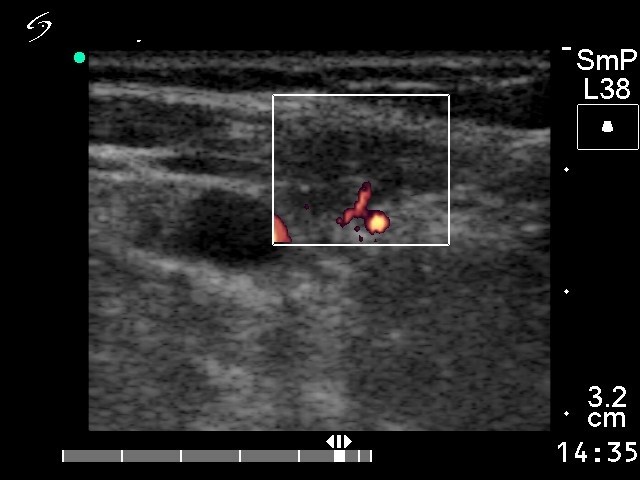

Ultrasonography revealed a hypoechogenic mass in the right lobe and in the isthmus with small cystic areas. The nodule was avascular on Doppler mode.